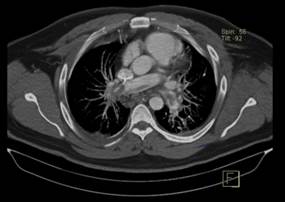

A las 48 horas de ingreso en UCI presenta de forma súbita deterioro hemodinámico e hipoxemia refractaria que no mejoraba, a pesar de encontrase en decúbito prono y con parámetros ventilatorias adecuados. Se procedió a realizar ecocardiograma (Fig. 1) que reporta ventrículo izquierdo con  diámetros conservados, motilidad conservada, función sistólica FEVI 61% por Simpson, cavidades derechas dilatadas VD 4.2 basal,  TAPSE 1 cm, onda S 0.07 m/seg, vena cava 1.7 cm, en el eco doppler llenado diastólico con patrón normal, insuficiencia tricuspidea moderada Vmax 3.2 m/seg, PSP aproximada 45 mmhg, disfunción sistólica del VD, dilatación de cavidades derechas.

Figura 1. Ecocardiograma previo a tratamiento fibrinolítico. A Disfunción sistólica de VD con TAPSE 1, B Insuficiencia tricúspidea con Vmax 3,2 m/seg , C Dilatación de cavidades derechas